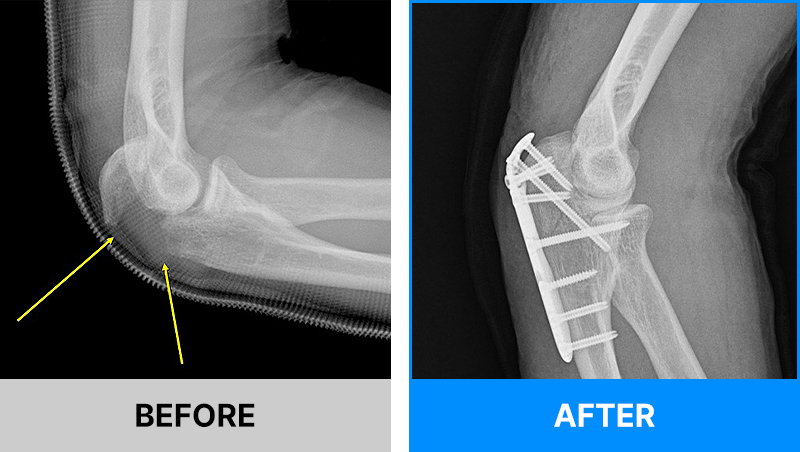

왜 당일 입퇴원 수술일까요?

오래 입원할 필요가 없기 때문입니다.

서울거탑정형외과에서는 전신마취, 척추마취가 아닌

국소부분마취(신경차단) 및 수면 마취를 통해 수술을 시행합니다.

수술 가능 여부 확인은 대표원장과의 진료가 필요합니다.